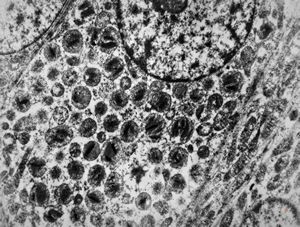

F,72y. | melanoblastoma oculi